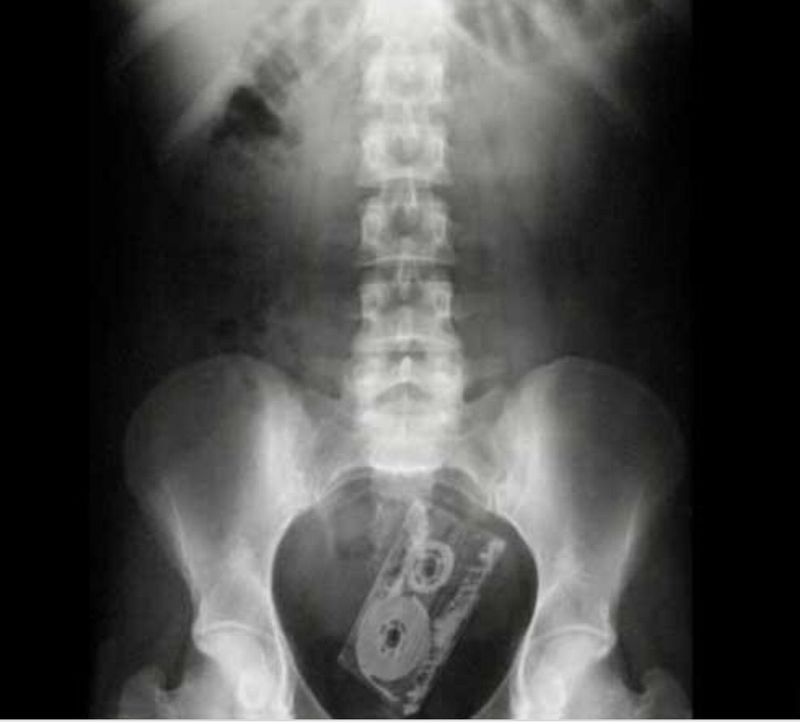

Casette

Weird cases

😂😂Ok so if you inserted a portable cassette player you could listen with your stethoscope😂

damn those horny patientsđŸ€ŁđŸ˜‚

‘I slipped and fell on it’